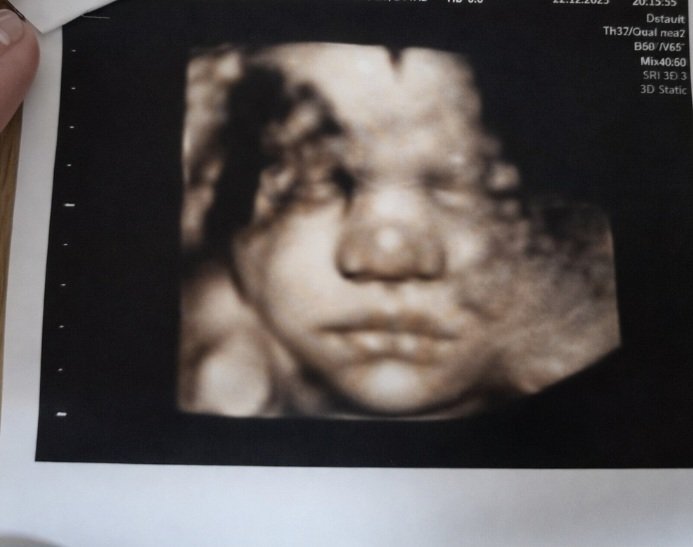

Хубавец, ще го вземаме за зет Simple Smile и нашето бебе беше сърдито на последната ФМ

Показвам ви моето момченце да го видите, тогава АГ каза, че нещо е сърдит 😄 може би да си е спял и ние сме го събудили ❤️